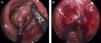

Se intervino bajo anestesia combinada, raquianestesia y general. Paciente en decúbito supino. Previamente al inicio de la cirugía, se exteriorizó de forma completa el prolapso. Este medía 10cm de longitud; se colocaron 2 puntos en su parte más distal, de forma que se tuviera como punto de referencia en la mucosa para valorar el límite de resección (fig. 1A).

Como utillaje de CET se utilizó el TEO (transanal endoscopic operation, K Storz, Alemania). Se procedió a la resección circunferencial del prolapso, mediante el bisturí ultrasónico (Ultracision, Ethicon, Endo-Surgery, Cincinnati, Ohio, Estados Unidos) abarcando toda la pared rectal, hasta la grasa perirrectal. La exéresis se realizó en 2 fases. En la primera, se marcó una circunferencia a unos 7cm del margen anal (fig. 1B). Se inició la exéresis circunferencial, desde la línea pectínea hasta la zona señalada. Una vez finalizada esta fase se reintrodujo el rectoscopio hasta el límite de resección y se marcó otra circunferencia hasta unos 5cm más allá de los puntos de referencia que se habían marcado al inicio, con la exteriorización de todo el prolapso (fig. 2A). Se volvió a realizar una nueva exéresis circunferencial de toda la pared rectal. No existió perforación en cavidad abdominal ni sangrado significativo.